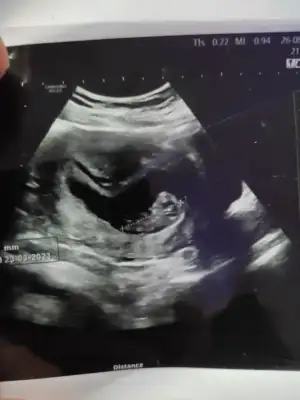

Omfalosel durumu vardı. Yani bebeğin karın duvarı kapanmadığı için iç organları karın boşluğu dışında yüzüyordu. Bu tüm bebeklerde gelişimin bir parcasi fakat 10. haftada organlar karın boşluğuna girerek karının iki yandan birleşmesi gerekirken bizim 10+5te halen kapanmamıştı. Doktorum da son tarih olarak 11+5 i bekleyip ona göre eğer kapanmadaydi ek tahliller yaparak deformasyonun boyutunu ve organ hasarlarına bakacaktı. Ama gerek kalmadı kapanmış....

Bu arada cinsiyet içinde tahminde bulundu